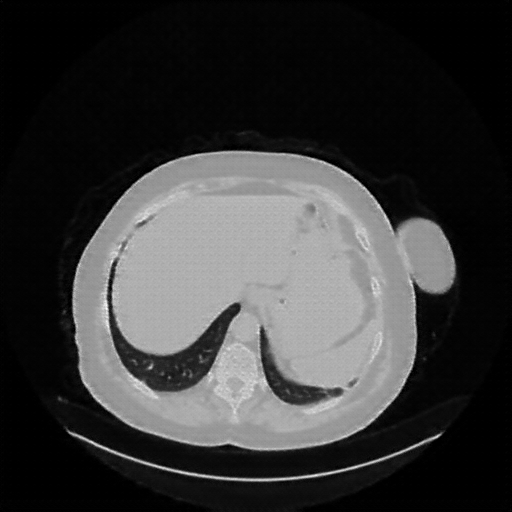

Image Grid

4Γ—3 grid: Rows show different image types (Original NATIVE, Reconstructed NATIVE, Original VENOUS, Generated VENOUS), Columns show windowing techniques (No Window, Lung Window, Mediastinum Window)

Generated VENOUS CT scan (A→B translation)

Full window (WL 1023.5, WW 4095 β†’ Low βˆ’1024, High +3071)

Lung window (WL -600, WW 1500 β†’ Low βˆ’1350, High +150)

Mediastinum window (WL 40, WW 400 β†’ Low βˆ’160, High +240)